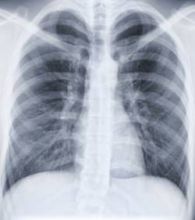

De nouvelles molécules contre les cancers du poumon

https://www.sante-decouverte.com/wp-content/uploads/imgsd/de-nouvelles-molecules-contre-les-cancers-du-poumon_s.jpgL’équipe du Dr Janne de l’Institut contre le cancer de l’hôpital Brigham de Boston a mis au jour de nouvelles molécules capables de traiter des formes de cancer du poumon  résistantes aux traitements.

Les chercheurs ont procédé à des tests sur des souris atteintes de cancers du poumon « non à petites cellules ». Ces types de cancer représentent 70 à 80 % de l’ensemble des cancers du poumon constatés : certains sont porteurs d’une mutation spécifique entraînant la production d’une protéine appelée facteur de croissance épidermique (EGFR).

Il existe des médicaments capables de bloquer l’action des récepteurs de cette protéine, mais des mutations génétiques ont été constatées sur certaines tumeurs, engendrant une résistance à ces traitements. Les nouvelles molécules développées par l’équipe du Dr Janne s’attaquent aux mutations tout en inhibant la production de la protéine.Les chercheurs espèrent que ces molécules seront mieux tolérées que les médicaments inhibiteurs actuels. Ils doivent désormais prouver l’efficacité de leur découverte à l’échelle humaine mais restent très optimistes quant à son potentiel.